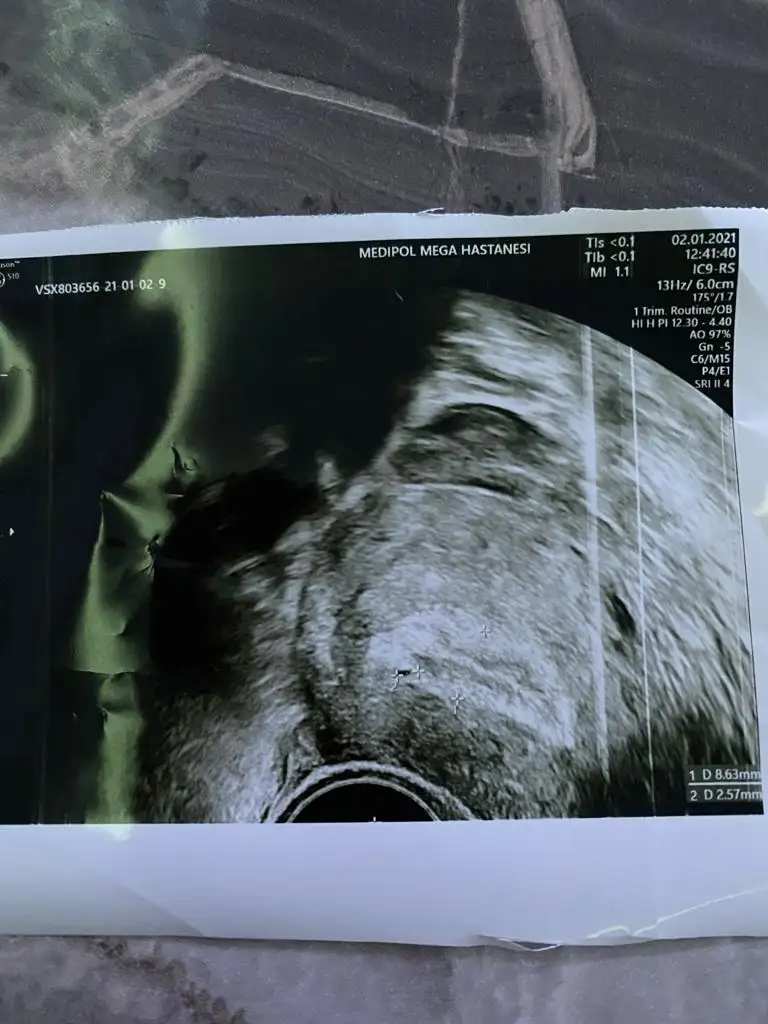

canım bence burda oluşan yapıyı görüdğü için tüpler temiz demiş olmalı. arkadaşımın bir dıktorun bebek dediğine ertesi gün başka doktor kanama alanı bu dedi düşük yaptı.